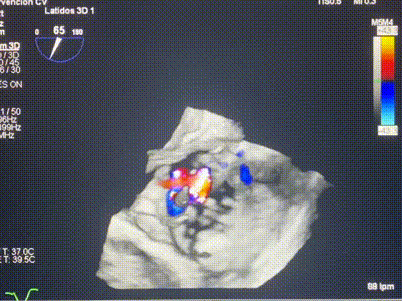

術中輸送器在超聲引導下調整位置

手術在全麻狀態下進行。術者采用經右側頸靜脈入路的方式將輸送器送入患者心臟內,在TEE及DSA引導下調整輸送器頭端角度,使得輸送器與三尖瓣瓣環平面垂直。在輸送器進入右心室后釋放室間隔錨定裝置,而后釋放瓣葉夾持件(2個耳片結構)成垂直狀態。在TEE及DSA確定夾持件固定至三尖瓣葉根部且位于右室側后釋放人工瓣心房側盤片。隨后調整瓣膜同軸性以及室間隔錨定件位置(貼合室間隔),前推藏針管并固定,進而釋放室間隔錨定裝置,并再次確認瓣膜位置、穩定性及同軸性,合攏輸送鞘后撤出輸送器,完成LuX-Valve Plus人工三尖瓣瓣膜的植入,僅殘余微量瓣周漏。且經手術中心電生理團隊評估,病人的起搏器和ICD功能沒有受到影響。